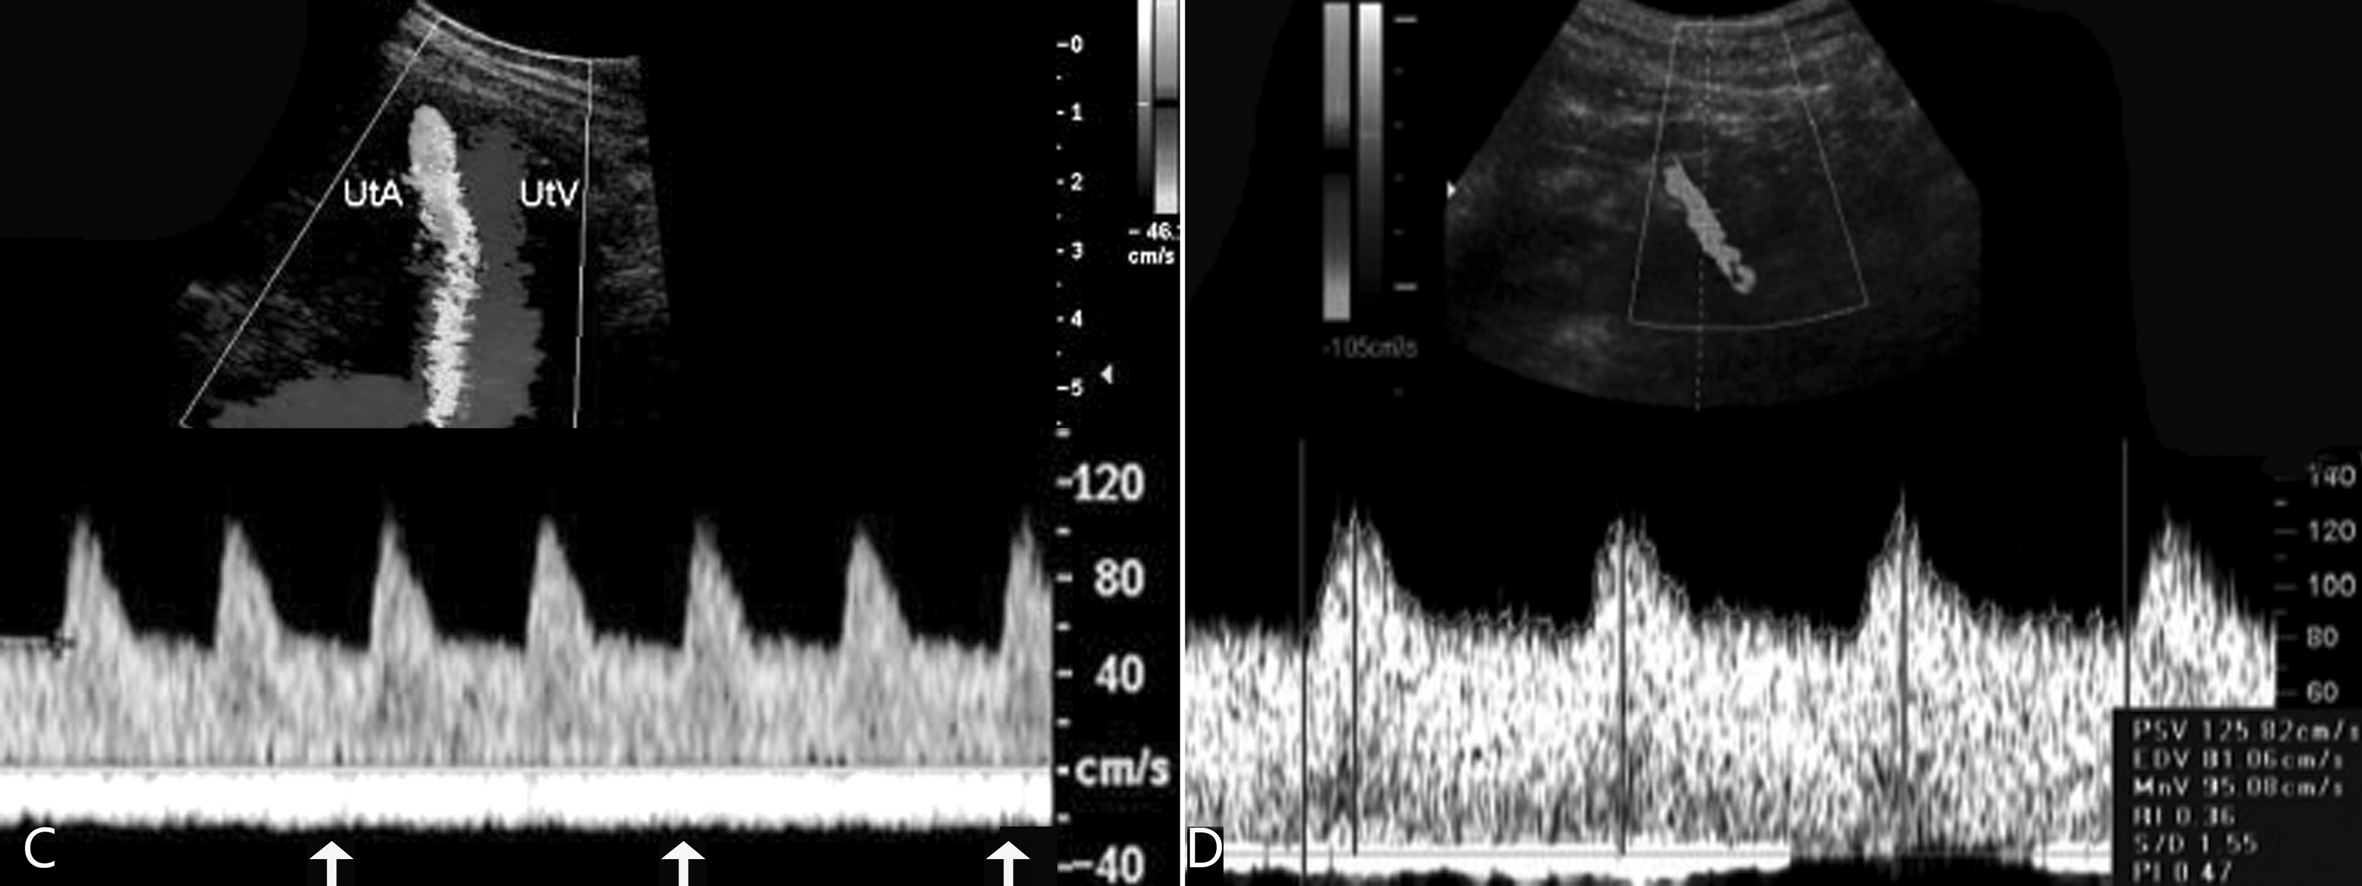

检查时需要注意部分孕妇的双侧子宫动脉血流速度曲线在舒张早期会显示一个向下的凹陷,称为舒张早期切迹(PN)(图5)。曾经认为子宫动脉血流速度曲线的舒张早期切迹与不良妊娠过程有一定的关系,但Gomez等在他们的研究中发现PN在整个妊娠期都可能出现,但愈到晚期PN的发生率越低,11~14周时发生率为46.3%,15~24周发生率为16.5%,24周至足月其发生率为5%。Souza等观察使用硫酸镁治疗严重的产前子痫病人时可以明显改善孕妇的子宫动脉PI,降低孕妇心率,但对PN没有明显的影响。提示某些病人PN的存在并不意味着都会伴发病理性变化,而子宫动脉PI的变化或二者结合可能更有意义。

图5妊娠期子宫动脉血流速度曲线的比较

A:妊娠中晚期正常子宫动脉血流速度曲线

B:妊娠期子宫动脉血流速度曲线的舒张早期切迹(箭头)